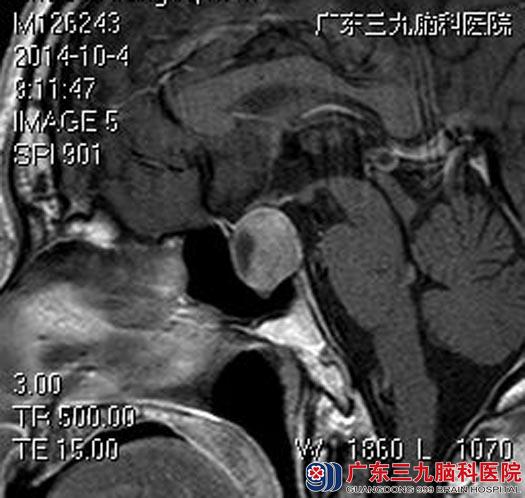

之后,他来到了广东三九脑科医院,头颅MR检查提示:鞍内及鞍上示一不规则异常信号影,范围约为1.86×1.90×2.78cm。脑桥、中脑、双侧基底节区-放射冠区散在陈旧腔梗灶。

手术前